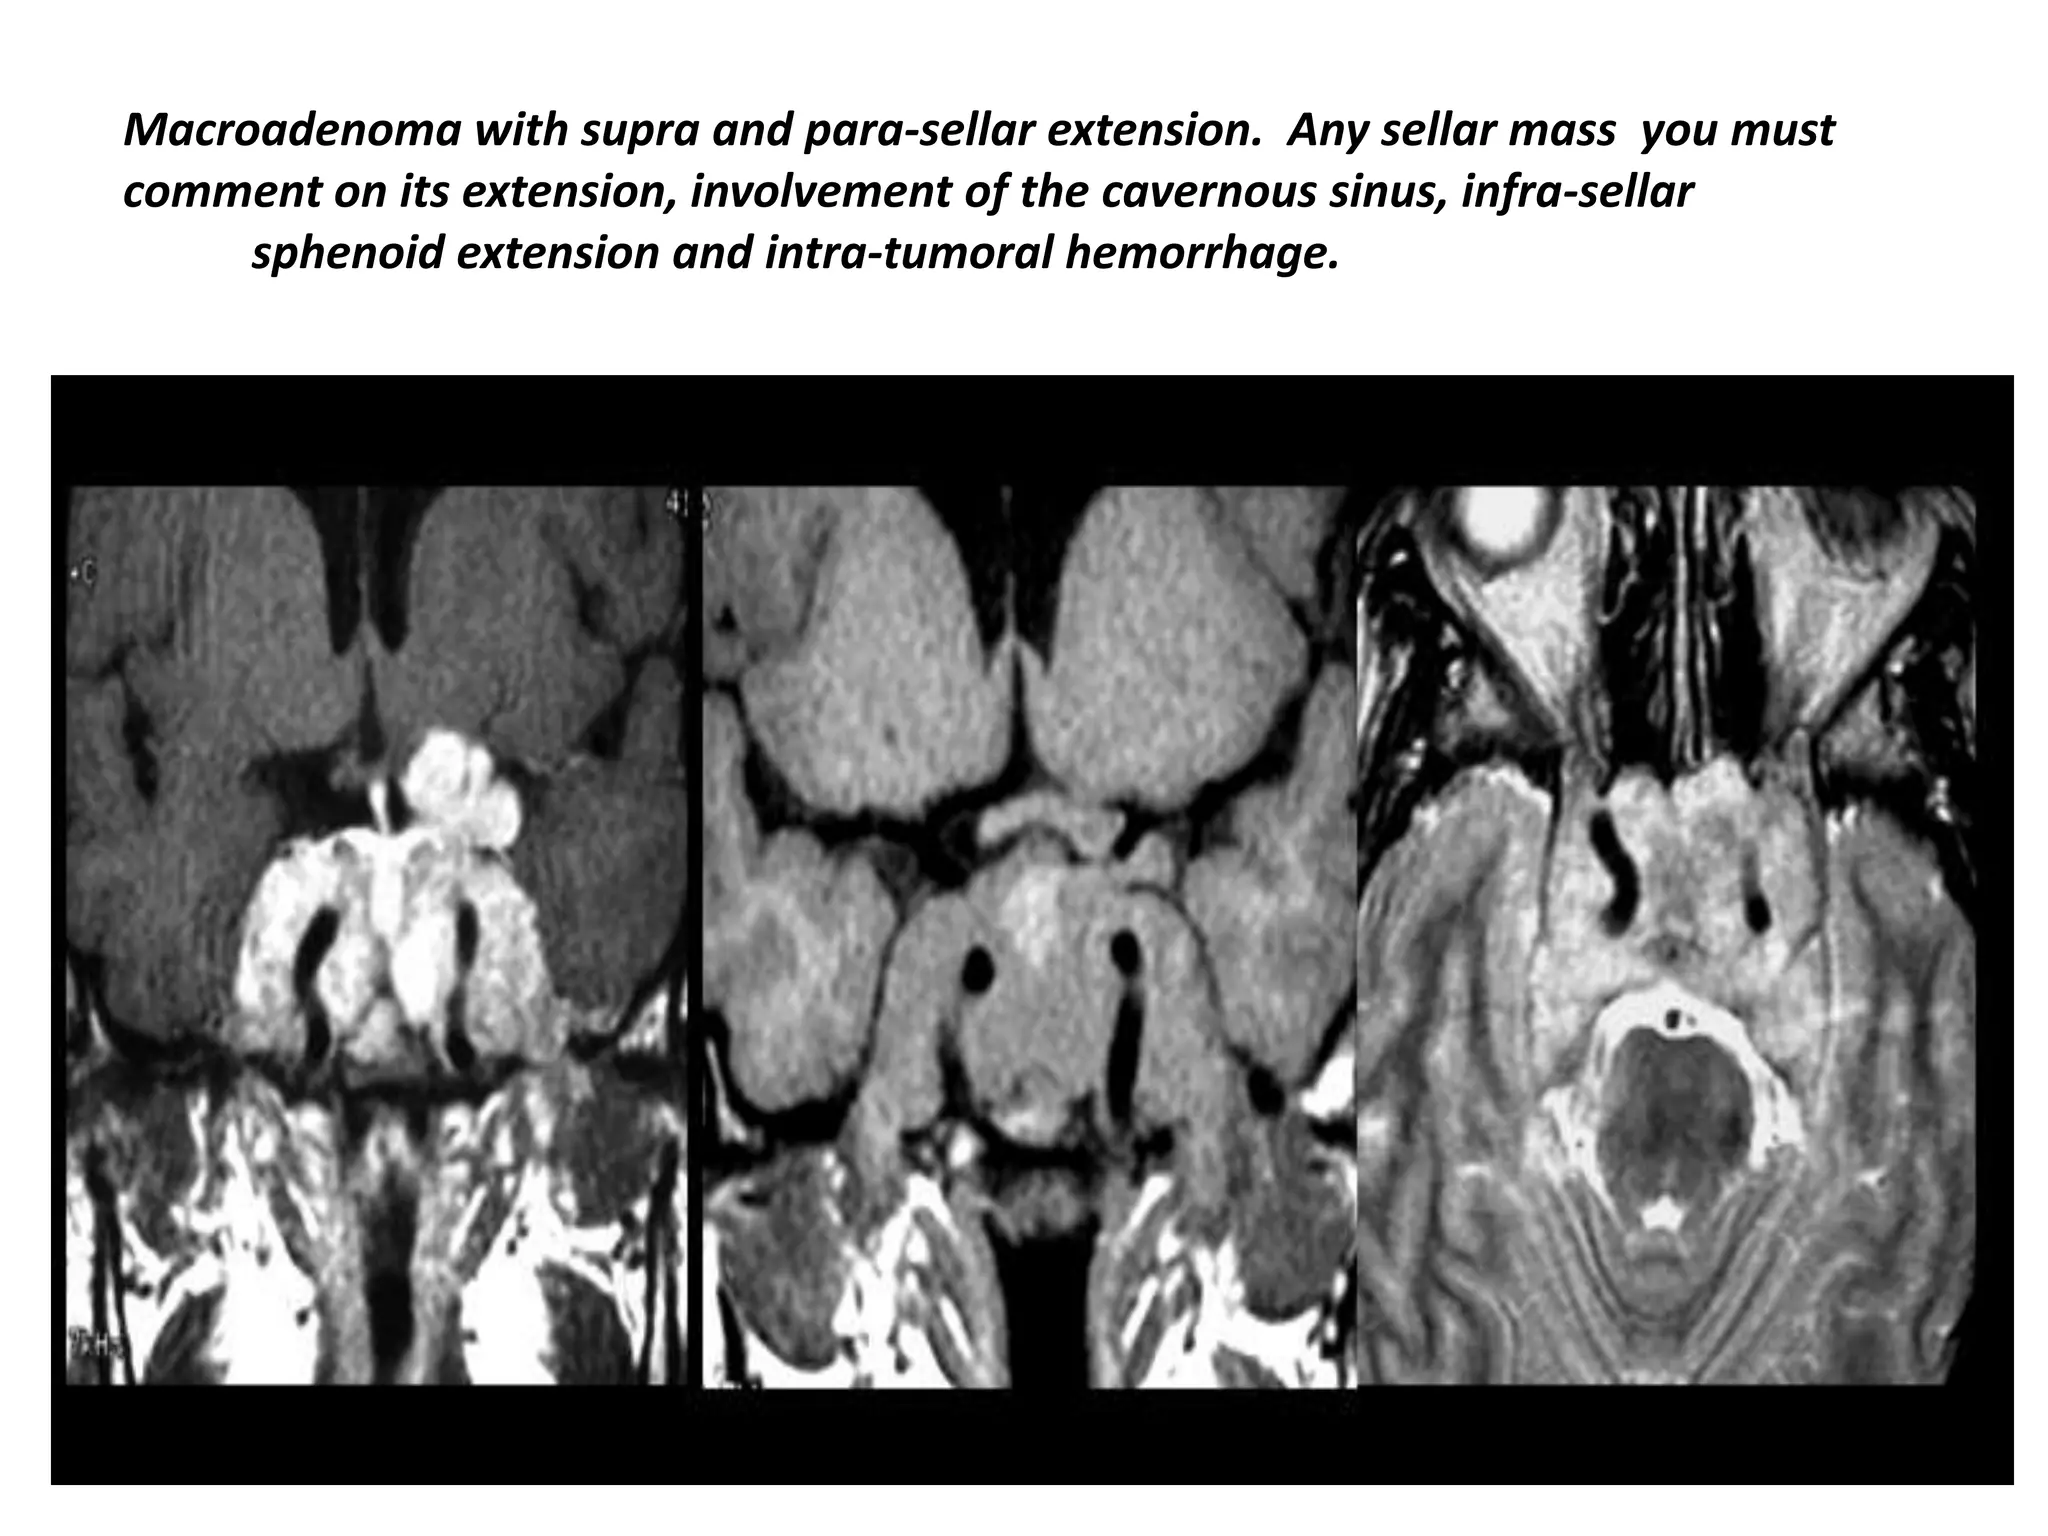

Macroadenoma with supra and para-sellar extension. Any sellar mass you must

comment on its extension, involvement of the cavernous sinus, infra-sellar

sphenoid extension and intra-tumoral hemorrhage.